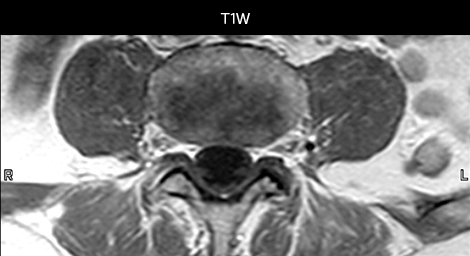

„Mit mDIXON TSE-Sequenzen ist es dank der T2-gewichteten Bilder auf Wasserbasis aus derselben Erfassung möglich, gleichzeitig morphologische Veränderungen aus den T2-gewichteten In-Phase-Bildern zu charakterisieren und ödematöse Veränderungen darzustellen. Auf diese Weise können anatomische und morphologische Befunde wie eine partielle oder komplette Bandruptur, ein knöcherner Ausriss oder ein Hämatom abgeklärt werden.“ „In Bezug auf die Beurteilung von Weichteilgewebe bietet mDIXON ähnliche Vorteile. Bei einer T2-gewichteten mDIXON TSE-Erfassung helfen die multiplen Kontraste zum Beispiel bei der Abklärung von pathologischen Befunden in Faserbündeln der peripheren Nerven, die auf anatomischen oder entzündlichen Veränderungen beruhen können.“ „Bei peripheren Gelenken erhalten wir mit mDIXON TSE eine gute Qualität in diffizilen Bereichen. Bilder mit Fettsuppression erscheinen vollständig homogen, auch bei einer großen Abdeckung mit 3,0 T – zum Beispiel beim Schulter- oder Beckengürtel – bzw. in den Gelenkflächen oder um Metallprothesen herum*, wo eine Fettsuppression mit STIR oder spektraler Suppression häufig unzureichend ist und zu Schwierigkeiten bei der Diagnose führt. Wenn ein diagnostisches Bild auf Anhieb richtig dargestellt wird, ist es nicht nötig, eine Sequenz zu wiederholen oder hinzuzufügen.“ „Mit mDIXON TSE-Sequenzen ist es dank der T2-gewichteten Bilder auf Wasserbasis aus derselben Erfassung möglich, gleichzeitig morphologische Veränderungen aus den T2-gewichteten In-Phase-Bildern zu charakterisieren und ödematöse Veränderungen darzustellen. Auf diese Weise können anatomische und morphologische Befunde wie eine partielle oder komplette Bandruptur, ein knöcherner Ausriss oder ein Hämatom abgeklärt werden.“ „In Bezug auf die Beurteilung von Weichteilgewebe bietet mDIXON ähnliche Vorteile. Bei einer T2-gewichteten mDIXON TSE-Erfassung helfen die multiplen Kontraste zum Beispiel bei der Abklärung von pathologischen Befunden in Faserbündeln der peripheren Nerven, die auf anatomischen oder entzündlichen Veränderungen beruhen können.“

„mDIXON TSE wird in unserer Notaufnahme ausgiebig für die Wirbelsäulenbildgebung eingesetzt“, führt Dr. Karis aus. „Besonders vorteilhaft ist, dass dieses Verfahren im Hinblick auf suszeptibilitätsbezogene Probleme sehr stabil ist, die häufig bei klassischen spektralen, fettgesättigten Bildern auftreten. Im Wesentlichen treten derartige Probleme beim mDIXON-Verfahren überhaupt nicht auf. Wir sind wirklich froh, in unserer Notaufnahme über die fettfreie Bildgebung des mDIXON-Verfahrens zu verfügen.“

„Für die routinemäßige, kontrastmittelfreie Untersuchung der Brust- und Halswirbelsäule führen wir zum Beispiel eine mDIXON T2-TSE-Sequenz durch, die uns zwei Ergebnisse liefert: die T2-gewichteten Bilder auf Fett- und Wasserbasis sowie die sagittalen T2-gewichteten Bilder auf reiner Wasserbasis. Anschließend erfolgt noch eine axiale Gradientenecho-Untersuchung.“